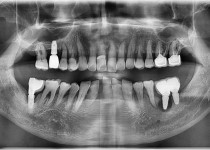

만 52세 전악 상악, 하악 전체 임플란트…

만 56세 상 하악 임플란트 증례